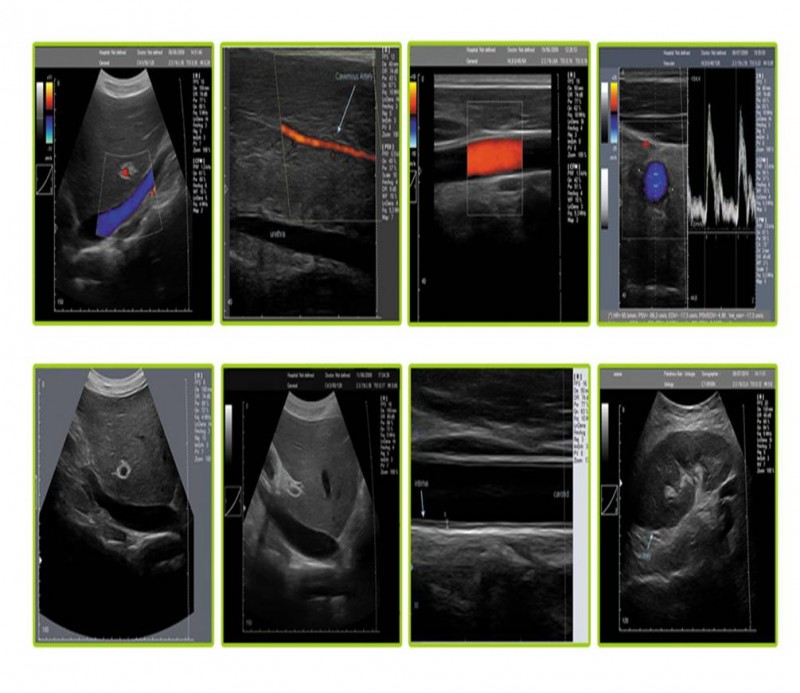

超聲多普勒穿刺 PICC置管 超聲介入 靜脈置管產(chǎn)品說明:

?超聲介入引導(dǎo)系統(tǒng)是針對(duì)經(jīng)外周靜脈穿刺中心靜脈置管(PICC)、靜脈中心置(CVC)和各種類型的神經(jīng)阻滯等手術(shù)可視化需求而專門設(shè)計(jì)的一款??朴貌食E溆歇?dú)特的穿刺引導(dǎo)系統(tǒng),在幫助醫(yī)護(hù)人員獲得高質(zhì)量超聲圖像的同時(shí)通過智能化操作引導(dǎo)功能,進(jìn)行快捷、方便的診斷操作。

超聲介入引導(dǎo)下的深靜脈穿刺和各種類型的神經(jīng)阻滯利用超聲原理實(shí)現(xiàn)可視化技術(shù),已經(jīng)逐步成為麻醉學(xué)科發(fā)展的重要方向,另外在淺靜脈置管、PICC置管、CVC置管、胸腔穿刺、術(shù)中影像檢測(cè)、在腫瘤科、神經(jīng)外科、腎內(nèi)科ICU、急診急救等方面也廣泛應(yīng)用。